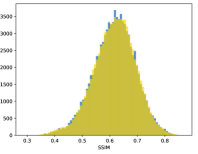

To visualise similarity metrics that compare image pairs (RMSE, SRE, SSIM) two metric distributions are generated: intra-similarity and inter-similarity. For each compared sample 300 random images are selected. The inter-similarity distribution is calculated for each image pair combination from both compared samples e.g. generated images of COVID-19 and real images of COVID-19. For the intra-similarity, all pairs of images in a single sample e.g real images of COVID-19 are considered. By comparing the shape of intra-similarity for the training subsample (Dataset) with the inter-similarity of training and generated samples the quality of the generated sample can be judged. It is also possible to compare in this way between the four image classes present in the dataset. The resulting distributions of inter-similarity of COVID-19 and the three remaining classes are compared in Fig. 4 to distributions of intra-similarity of the COVID-19 sample for each metric. All metrics, as expected based on available medical evidence Rubin et al. (2020), indicate that there are visible differences not only between COVID-19 and normal samples but also between viral pneumonia and lung opacity. Therefore, all classes should be distinguishable.

To visualise differences between synthetic and real samples distributions are generated for each of the RMSE, SRE and SSIM metrics: intra-similarity and inter-similarity. For each compared sample 300 random images are selected. The inter-similarity distribution is calculated for each image pair combination from both compared samples e.g. generated images of COVID-19 and real images of COVID-19. For the intra-similarity, all pairs of images in a single sample e.g real images of COVID-19 are considered. The distributions for generated samples describe very well the distributions for corresponding real images as shown in Fig. 6.

The quality of generated images is also confirmed with classical similarity metrics. The distributions of those similarity measures between generated and real images are compared for each sample with the distribution obtained within the real samples 6. The distributions for generated samples describe very well the distributions for corresponding real images. For an example see the results for the SSIM metric presented in Fig. 10. The small visible differences are almost insignificant compared to differences observed between the classes in Fig. 4.